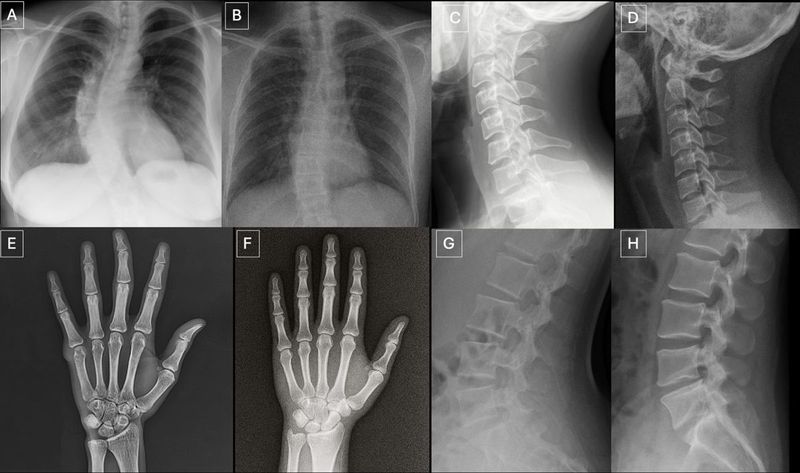

『Radiology』掲載論文より、解剖学的構造が一致した実際のレントゲン写真(A、C、E、G)と、GPT-4oで生成したレントゲン写真(B、D、F、H)。(https://pubs.rsna.org/doi/10.1148/radiol.252094 © 2026 by the Radiological Society of North America, Inc.)